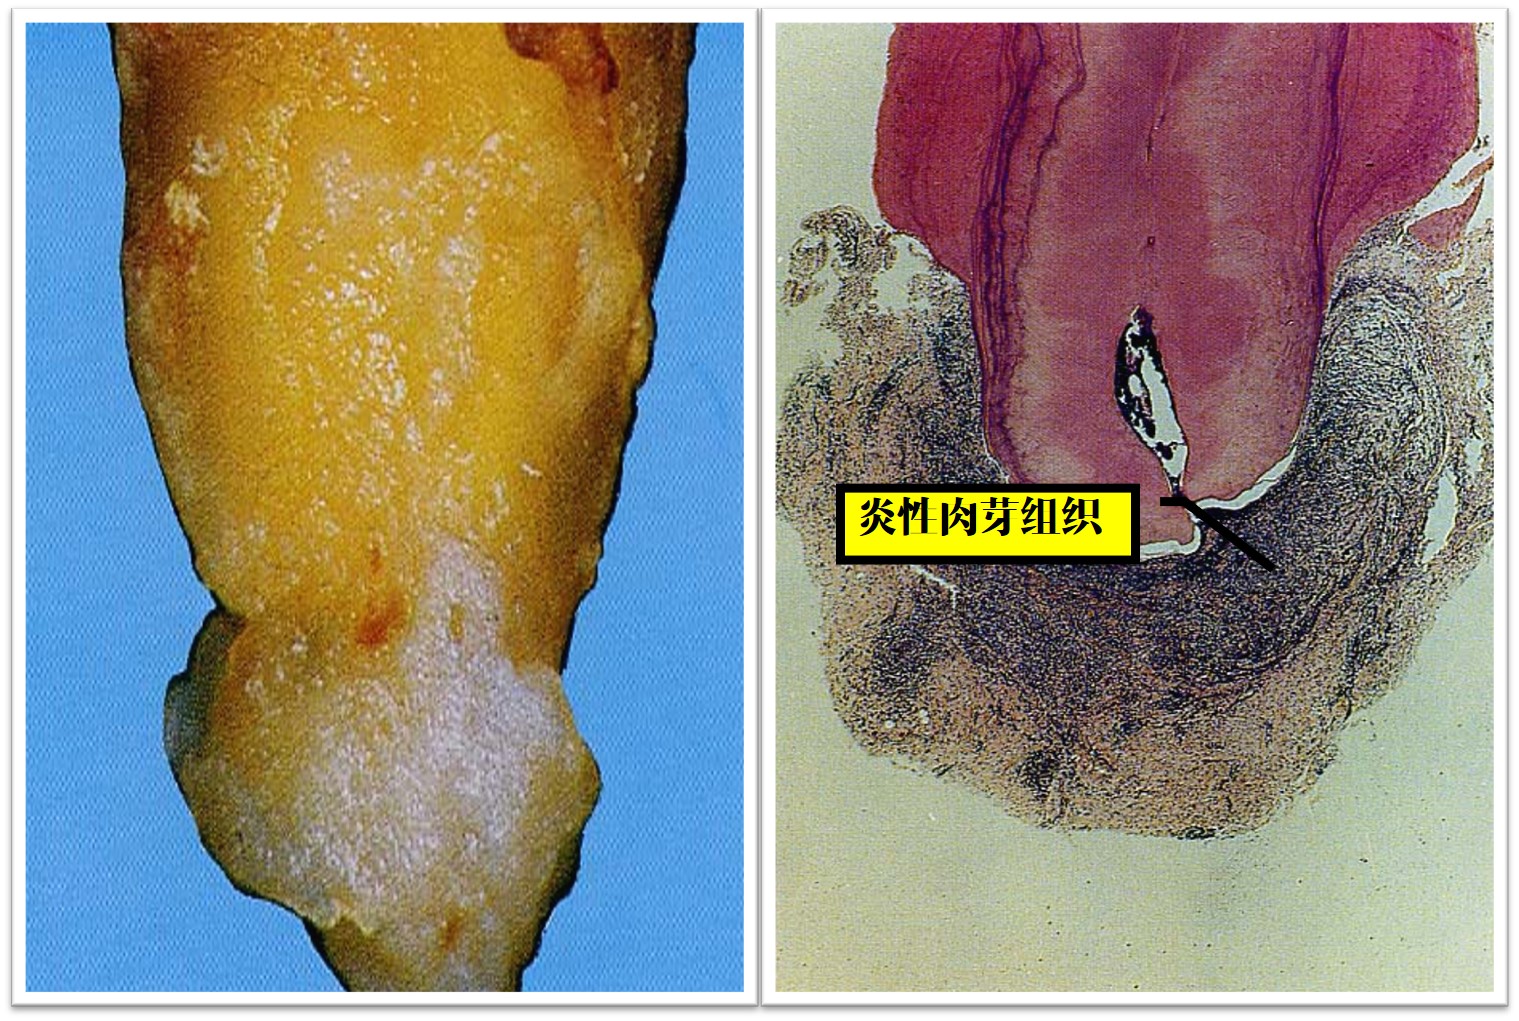

2)病理变化

早 期:根尖周牙周膜血管扩张,组织水肿,肉芽组织增生,慢性炎细胞浸润,范围局限于根尖周牙周膜。

后 期:炎症范围逐渐扩大,根尖周组织结构破坏,代之以炎性肉芽组织,周围纤维组织增生(图9.2-2)。肉芽组织中可见泡沫细胞、含铁血黄素及胆固醇结晶。

图9.2-2 根尖周肉芽肿

2)病理变化(图9.2-5)

1. 根尖有脓性分泌物黏附,粗糙不平,根尖区牙周膜内脓肿形成。

2. 脓肿中央为液化坏死组织和脓细胞,周围为炎性肉芽组织,散在炎细胞浸润和新生毛细血管,外有纤维结缔组织包绕。

3. 根尖牙骨质和牙槽骨有不同程度吸收。

图9.2-5 根尖周脓肿